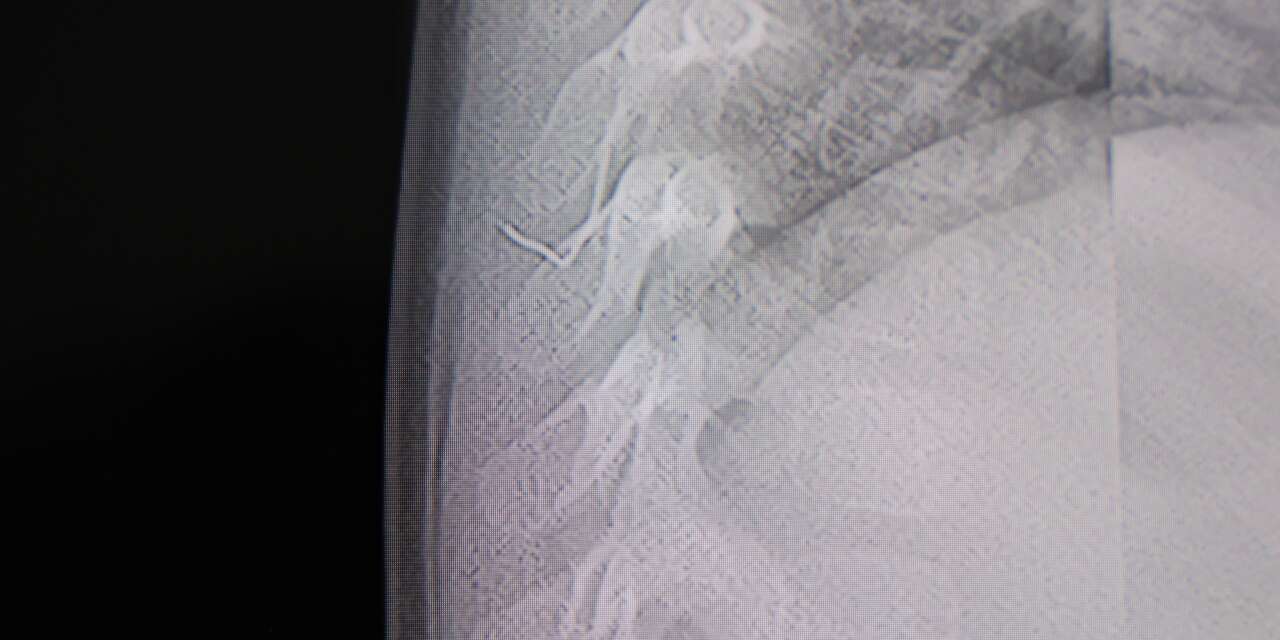

Kahramanmaraş'ta sırt üstü yatmak istemeyen ve yatırıldığında ağlayan bebeğin sırtından akciğer zarına doğru ilerleyen 2 santimetrelik zımba teli çıktı.

Hasta, genel anesteziye alınmadan, lokal anestezi ve sedasyon eşliğinde ameliyata alındı. Yapılan müdahalede yabancı cisim tamamen çıkarıldı. Çıkarılan cismin, ince zımba teline benzer metal bir tel olduğu ve yaklaşık 2 santimetre uzunluğunda bulunduğu tespit edildi. Hasta, aynı gün taburcu edildi.

Konuya ilişkin açıklama yapan Prof. Dr. İdris Altun, "Sırtında yabancı bir cisim olduğu söylenmiş ancak çıkarılamayacağı ve 8 yaşına kadar beklenmesi gerektiği ifade edilmişti. Bize başvurduğunda yaptığımız tetkiklerde, cilt altında, omurilik kanalına çok yakın ve akciğer zarına doğru ilerleyen bir yabancı cisim tespit ettik. Hastamızı tamamen uyutmadan, lokal anestezi ve sedasyon eşliğinde müdahale ederek lezyonu tamamen çıkardık. Çıkardığımız cismin ince zımba teline benzer, yaklaşık 2 santimetre uzunluğunda metal bir tel olduğunu gördük. Bu yabancı cisim alınmasaydı, bölgede enfeksiyon gelişebilirdi. Enfeksiyon sonucu omurilik kanalında ciddi hasarlar oluşabilir, çocuk büyüdükçe cismin hareket etmesine bağlı olarak omurilikte zedelenmeler meydana gelebilirdi. Ayrıca yana doğru ilerleyerek akciğer zarına ve akciğere batma riski vardı. Bu da enfeksiyona ve ilerleyen süreçte tümörle karışabilecek tablolara neden olabilirdi. Şu an hastamız gayet sağlıklı. Gerekli kontrolleri yaptık ve aynı gün taburcu ettik" dedi.